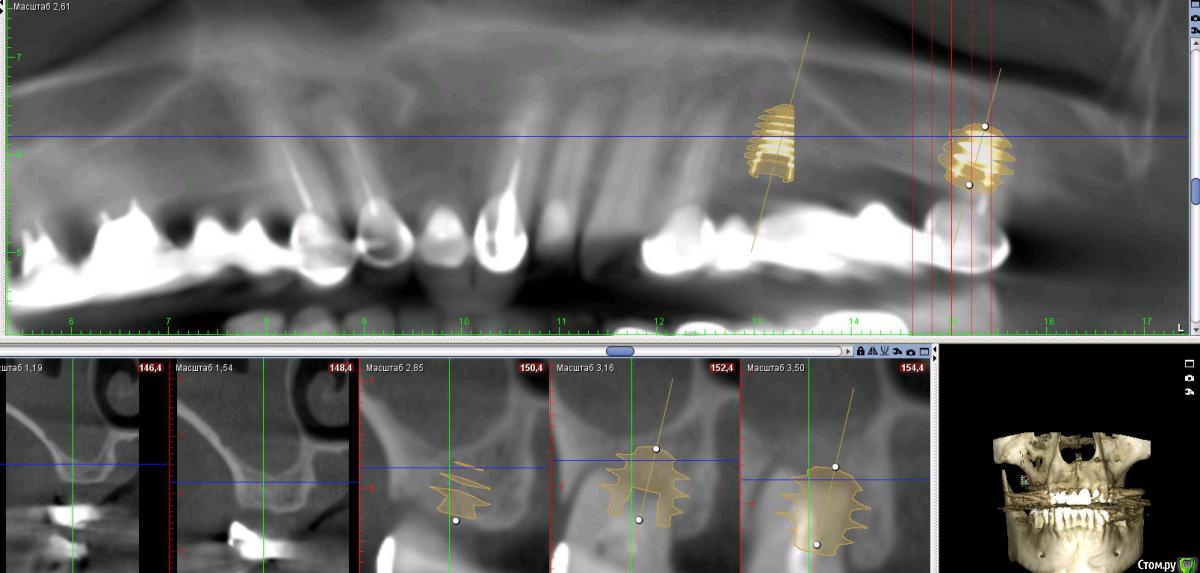

Дмитрий Л. Опубликовано 16 ноября, 2018 Поделиться Опубликовано 16 ноября, 2018 (изменено) Здравствуйте всем)Ситуация такая: старый мост 24-28. 28 симптоматичен, пациент принимает аб и противовосп. Имеется: - 24 перирадикулярные изменения (асимптомно)- 28 перирадикулярные изменения (обострение)- утолщение слизистой гайморовой (асимптомно)- невозможность имплантации в обл 26 (высота кости не позволяет) Пожелания пациента:- удаление 28 - желание сохранить мост - имплантация - нежелание носить съемную конструкцию Как планирую я:- перелечить 24, кальций 2-6 мес.- удалить 28- изготовить съёмник- выждать 4-6 мес. Повторить КТ, оценить гайморовую- имплантация 25, имплантация "где-то в обл 27" - всеми силами избежать синуса Мои грёзы:1. Ставить вблизи 24 - риск. Нужно лечить 24... реэндо... долго... может удалить? 2. Я верю, что причина хр гайморита - 28. Так ли это? Стоит ли ожидать позитивной динамики? 3. На сколько уйдёт кость после удаления 28 за 4-6 мес.? Её и так мало... Станет ли меньше? Графтить 28 не хочу. Там микробы. 4. Объём кости в обл 27-28 требует коротышку. Первыми приходят на ум Штрауман 6 мм (4 мм в кости, станет красиво) или ЭниРидж (бикортакально, скорее всего в пазуху на 1-2 мм). Нюанс в том, что я не работал этими системами... И коротышки не ставил. В общем придётся искать наборы, но это мои проблемы. 5. Итоговая конструкция: мост 25-27. При чём 27 имеет длину 4-6 мм, не слишком ли короткая дистальная опора? Вот спланировал приблизительно так... Надеюсь на отклик. Изменено 16 ноября, 2018 пользователем Дмитрий Л. Ссылка на комментарий

Bier Опубликовано 16 ноября, 2018 Поделиться Опубликовано 16 ноября, 2018 25-27 совершенно согласен. Я вангую, что и так туда 8мм войдет. Отрочено да. Я люблю отсрочено верхнюю челюсть делать. 1 Ссылка на комментарий

Neilrus Опубликовано 16 ноября, 2018 Поделиться Опубликовано 16 ноября, 2018 У эниридж есть совсем коротыши 5,5х5, для семерки, если не хотите лезть в синус самое то, у него огромная площадь получается за счет особенностей резьбы. Только для него набор специальный с ограничителями должен быть, но дилер может и даст в аренду за имплантат, покупать его не вижу смысла, нужен раз в полгода 1 Ссылка на комментарий